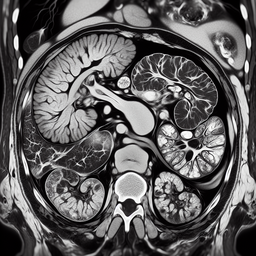

МРТ селезінки

МРТ селезінки — це неінвазивне діагностичне дослідження, яке використовує магнітні поля та радіохвилі для отримання детальних зображень селезінки.